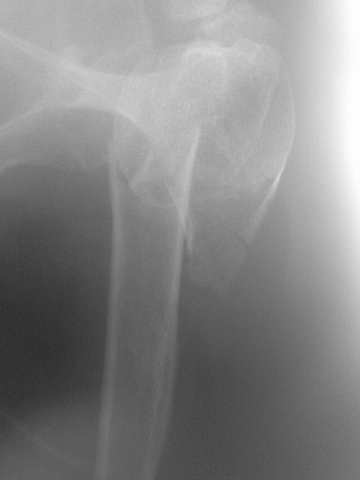

Hello,I am presenting a case of 80 year old male patient right handed known case of hypertension, diabetes and history of CVA 2 years back had a fall in the hosue 10 days back and came to me for pain and ecchymosis around the right shoulder. Xray shows evidence of comminuted fracture proximal humerus extraarticular. He is a doctors father and the doctor wants to know is there any minimally invasive procedure we can do ... I have advised him to go for complete surgery in the form of the AO locking plate under general anesthesia. He is a little reluctant for complete general anaesthesia. My questions to the house is ...1. Is there any other option besides the locking plate ?? (Less invasive) 2. If he is not medically fit for surgery, then can we leave him alone if yes what are the chances of going it into non union? Awaiting your reply Dr Neeraj Bijlani

CT scans would be useful to evaluate the head.

Another option could be closed nailing, see an example, the surgery was done 2 days ago. In common such surgeries are performed under regional anesthesia, not general.

One more option can be fixation by V-shape stressed wires.

Fragments now look severely displaced.